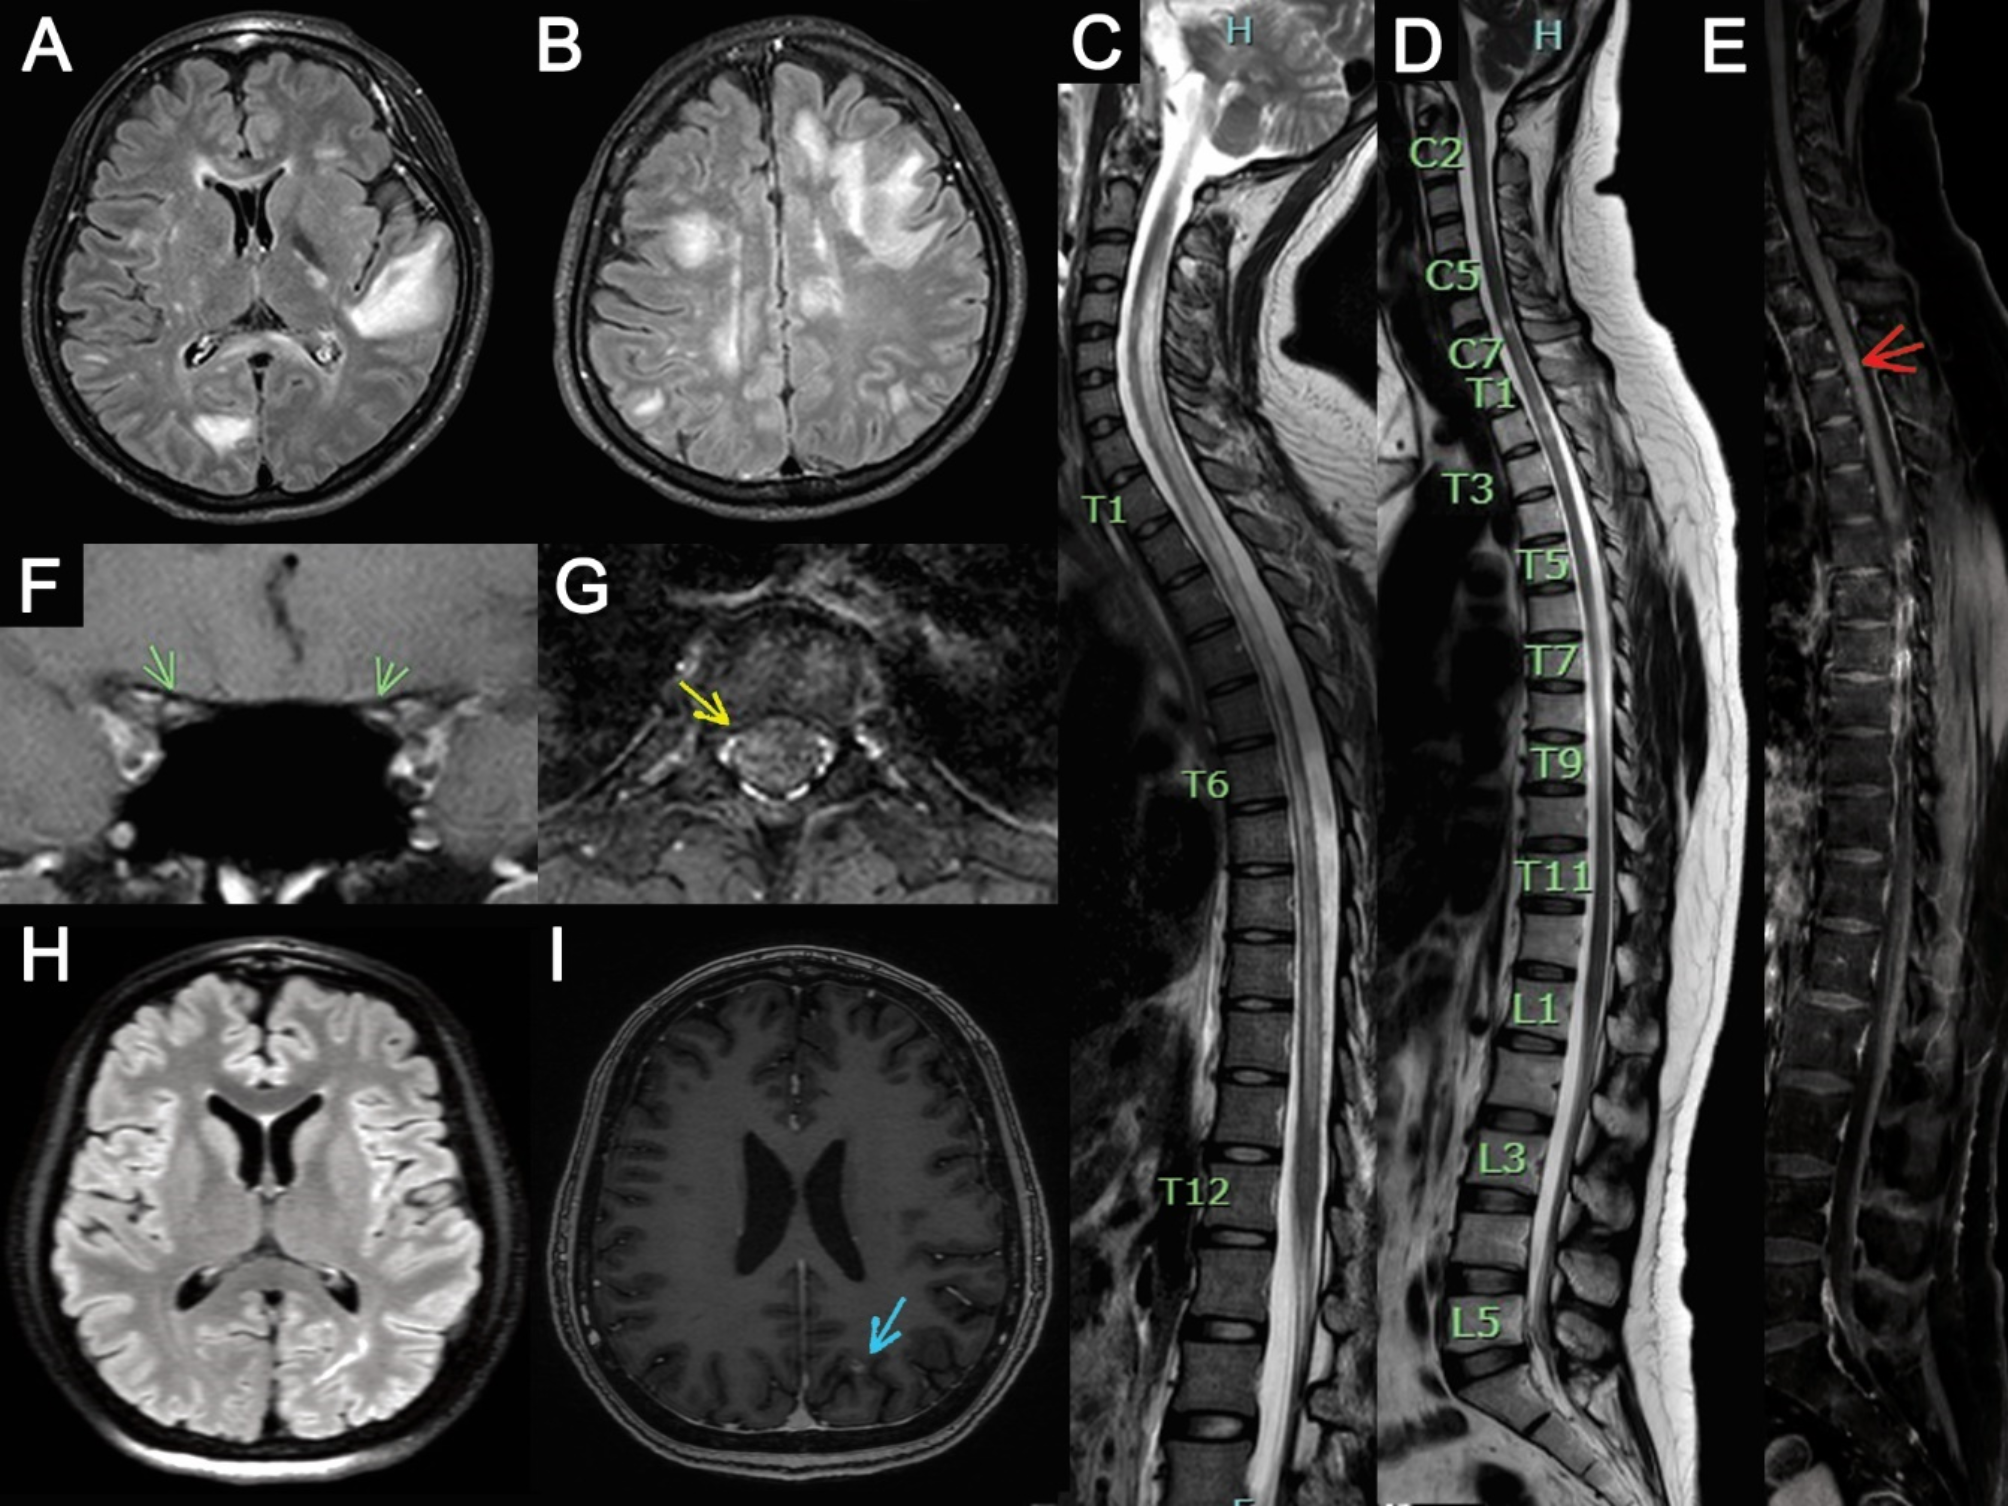

Fig. 4

Magnetic Resonance Imaging findings in this study. The first row displays the MRI of patient 4: (A-B) Axial brain MRI shows multiple abnormal T2 fluid-attenuated inversion recovery (FLAIR) hyperintense lesions at the subcortical white matter of the left temporal lobe, frontoparietal, right occipital, frontoparietal, and parietal lobe, and (C) Sagittal T2-weighted (T2W) MRI of the entire spine reveals a confluent long segment of abnormal hypersignal intensity along the cervical and thoracic vertebral levels. Spinal MRI of patient 5 is depicted in (D-E, G), showing multiple short segments of hypersignal intensity lesions on T2W along the lower C2-T7 level with faint enhancing foci at the ventral aspect at upper T3 levels (red and yellow arrows). (F) Coronal orbital MRI of patient 5 also reveals increased signal intensity on T2W (fat saturation) and gadolinium enhancement along both optic nerves from intraconal to prechiasmatic parts (green arrow). (H) The 2-month post-delivery axial brain MRI of patient 7 displays a new hypersignal intensity lesion on T2 FLAIR at the left occipital lobe, with (I) gadolinium enhancement (blue arrow).